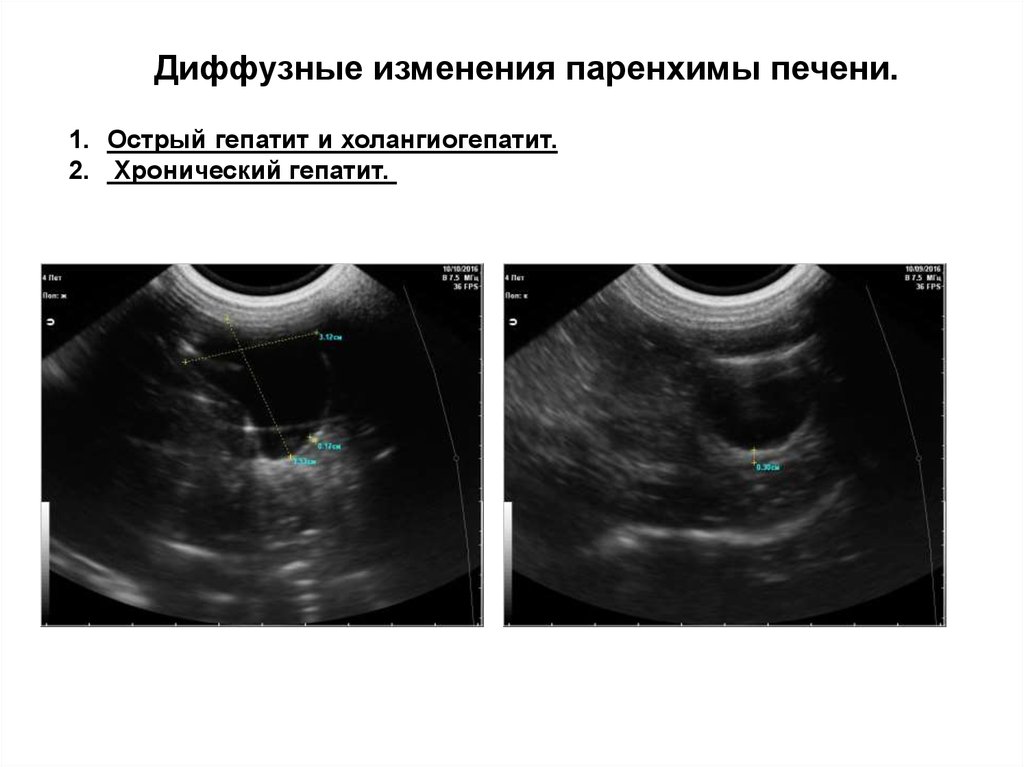

Диффузные изменения паренхимы печени.

1. Острый гепатит и холангиогепатит.

2. Хронический гепатит.